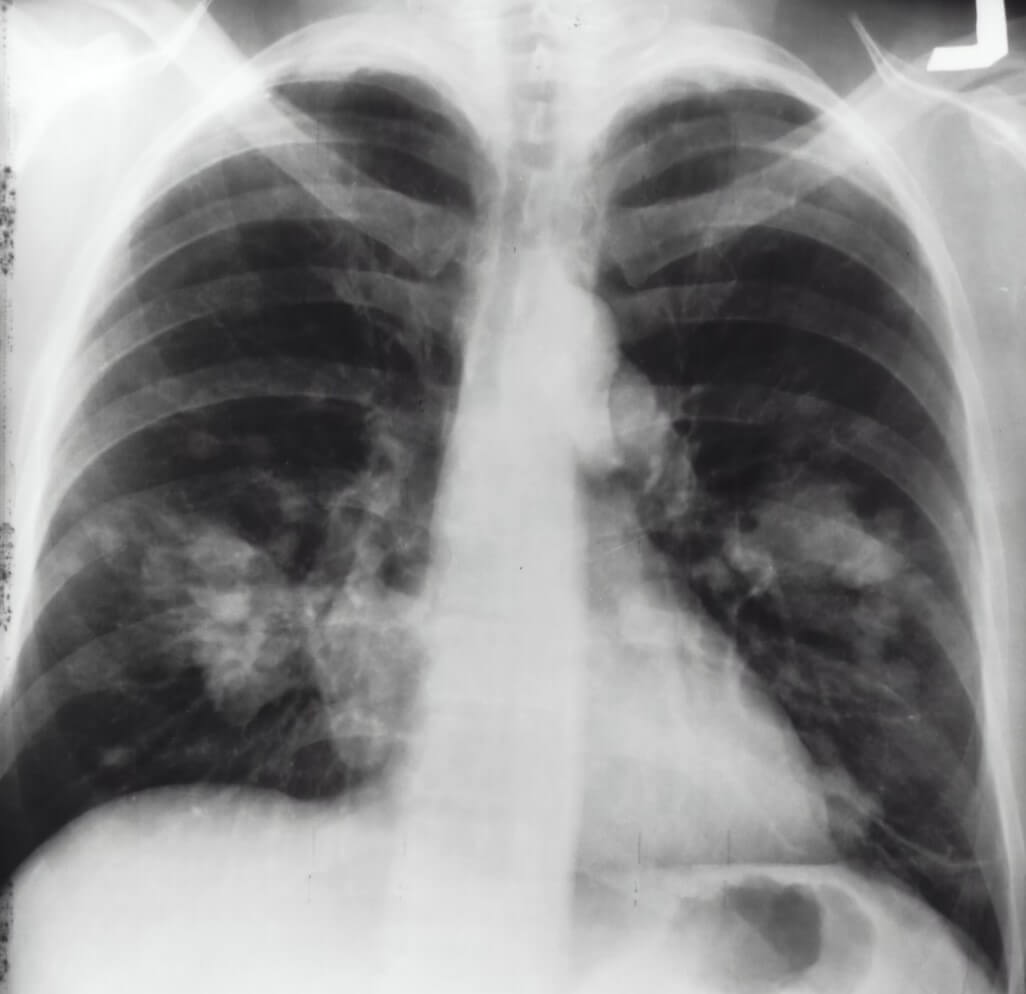

3) 환경 오염과 암

- 미세먼지, 중금속(납, 카드뮴) 등의 독소는 유전자 발현을 변화시켜 암 유발 가능성을 높임

- 특히, 흡연은 DNA 메틸화 변화를 유발하여 폐암과 관련된 유전자 발현을 촉진